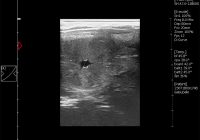

Evidence that embryo migration (translocation) is not always if ever, necessary for the successful signalling or reception of the Maternal Recognition of Pregnancy (MRP) in the mare – Long thought to be connected, embryo migration and maternal recognition may not be so closely related after all. By Professor John Newcombe, BVetMed, MRCVS A Case Study By tracking the… Read More »